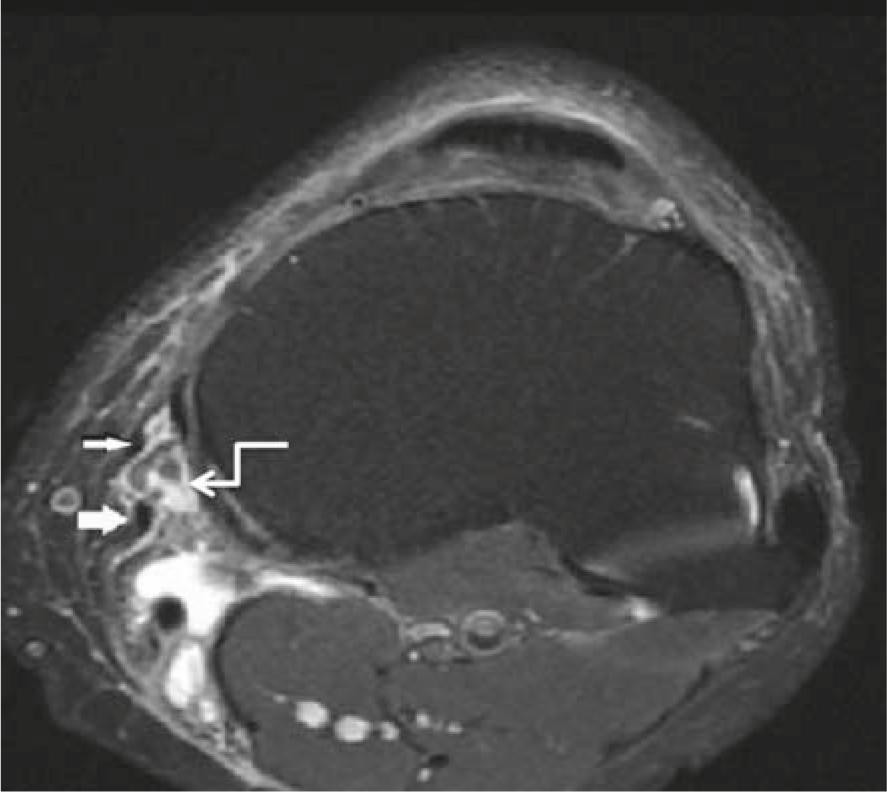

Bursitis was determined in at least one of the medial periarticular bursae in 41 patients, the most common form being PA bursitis (Figure 1). Bursitis cases determined at MRI are shown in Table 2. Presence of bursitis in the medial compartment was positively correlated with severity of OA, but was not correlated with CP (p = 0.023 and p = 0.479, respectively). The relation between medial meniscal tear, OA and CP and bursitis in the medial compartment is shown in Table 3. Baker’s cyst was determined in 36 patients, the prevalence increasing with severity of OA but was not correlated with CP (p = 0.044 and p = 0.264, respectively).

A 70 year-old patient presented with knee pain. Axial MR image shows sartorius (thin arrow) and gracilis tendon (thick arrow) in the patient with pes anserine bursitis (curved arrow).